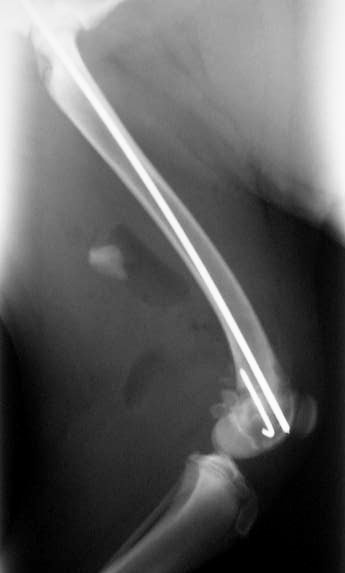

Υπερκονδύλιο κάταγμα μηριαίου σε σκύλο από Πέτρος Μπεάκος14/09/201307/12/2017Σχολιάστε Προεγχειρητική ακτινογραφία. Μετεγχειρητική ακτινογραφία:οστεοσύνθεση με διπλή ήλωση(ενδομυελικώς και χιαστί). Κοινοποιήστε: Στείλε ένα σύνδεσμο σε έναν φίλο(Ανοίγει σε νέο παράθυρο) Email Εκτύπωση(Ανοίγει σε νέο παράθυρο) Εκτύπωση Mοιραστείτε στο Facebook(Ανοίγει σε νέο παράθυρο) Facebook Μοιραστείτε στο X(Ανοίγει σε νέο παράθυρο) Χ Μου αρέσει! Φόρτωση... Σχετικά